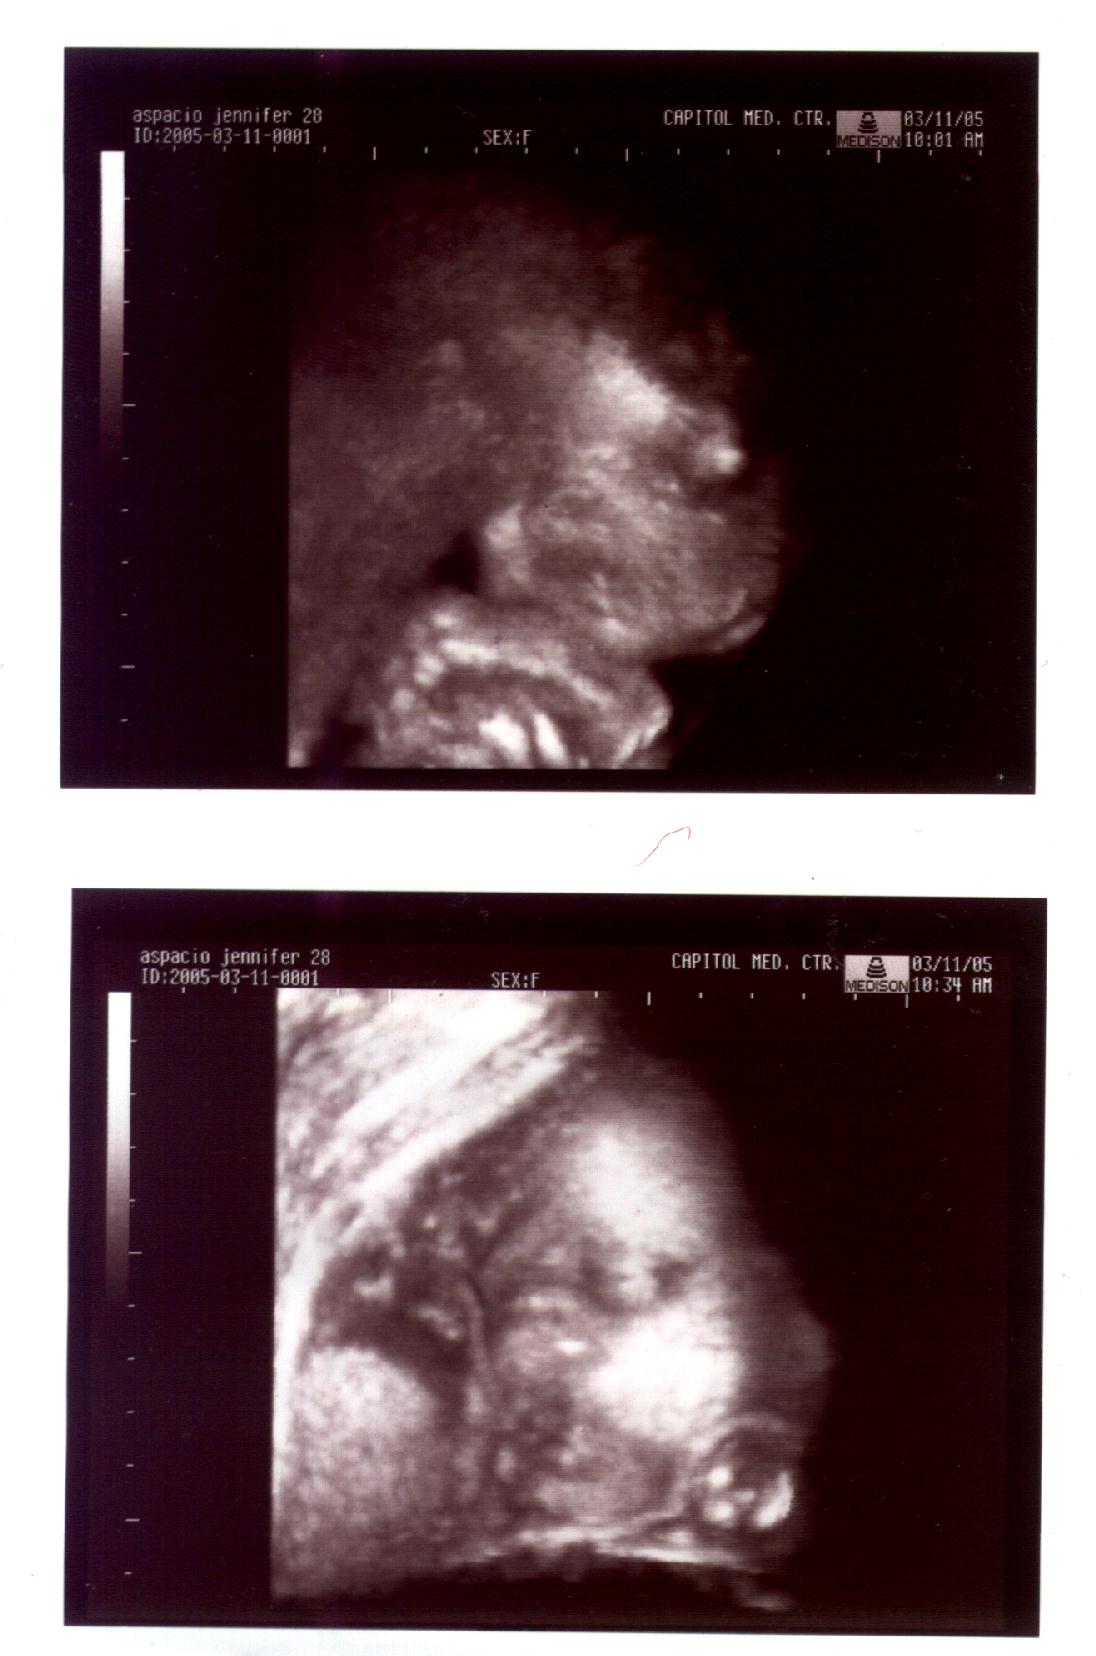

Right from when our son was in utero, the hubby and I were convinced that we are going to raise up not just a child we can live with, but a child who will be a blessing to others. Despite the many controversies Baby Wise has with a lot of attachment parenting groups, we held on and we have since seen the benefits it reaps our family, especially our little one. He is more social, bright and confident than children his age.

11 mos.‚1yr.‚ 1yr. 3mos.

1yr.,6mos.,2yrs.,9mos. 3yrs.(current)